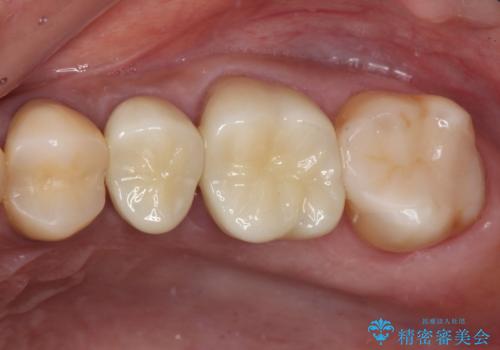

- 奥歯を治療しようと他院で開始したものの、放置してしまったとのことで来院された患者様です。

外れてしまった銀歯や穴の空いた仮歯などあり、適合の悪い被せものと合わせて、セラミッククラウンやセラミックインレーにて治療と行うこととしました。

億劫に感じて治療を先延ばししていたそうですが、始めてみるとスムーズに治療が終わり、早く始めておけば良かったと仰っていました。